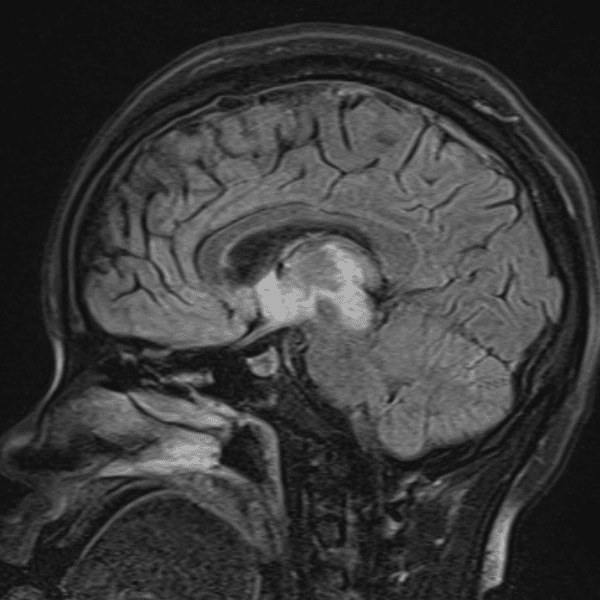

๋‹น์ง ์‹œ ํ”ํžˆ ๋ณผ ์ˆ˜ ์žˆ๋Š” ์‚ฌ๋ก€์˜ ์ „ํ˜•์ ์ธ ์˜ˆ๋ฅผ ํฌํ•จํ•ฉ๋‹ˆ๋‹ค.

39 ์‚ฌ๋ก€